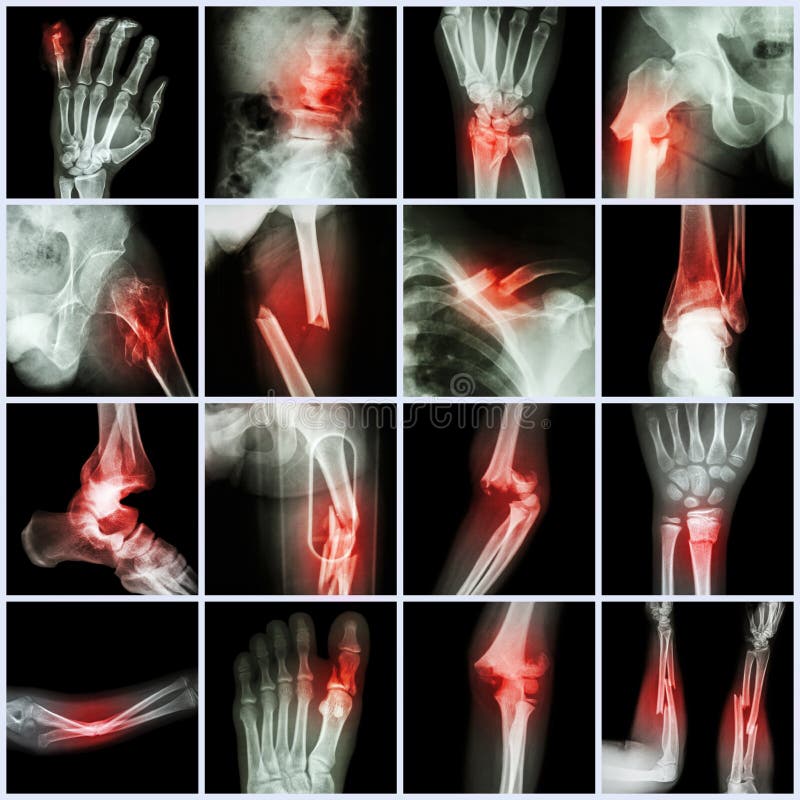

Radiologiczna wizerunku przedstawienia przełamu noga i przedramię. Radiologiczna wizerunku przedstawienia przełamu kość noga i przełamu dyszel ulnar przedramię